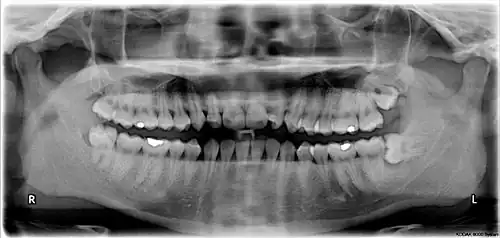

The third molar, commonly called wisdom tooth, is the most posterior of the three molars in each quadrant of the human dentition. The age at which wisdom teeth come through (erupt) is variable,[1] but this generally occurs between late teens and early twenties.[2] Most adults have four wisdom teeth, one in each of the four quadrants, but it is possible to have none, fewer, or more, in which case the extras are called supernumerary teeth. Wisdom teeth may become stuck (impacted)[3] and not erupt fully, if there is not enough space for them to come through normally. Impacted wisdom teeth are still sometimes removed for orthodontic treatment, believing that they move the other teeth and cause crowding, though this is disputed.[4][5]

Wisdom teeth (often notated clinically as M3 for the third molar) have long been identified as a source of problems and continue to be the most commonly impacted teeth in the human mouth. Impaction of the wisdom teeth results in a risk of periodontal disease and dental cavities.[29] Impacted wisdom teeth lead to pathology in 12% of cases.[30]

Impacted wisdom teeth are classified by the direction and depth of impaction, the amount of available space for tooth eruption and the amount of soft tissue or bone that covers them. The classification structure allows clinicians to estimate the probabilities of impaction, infections and complications associated with wisdom teeth removal.[31] Wisdom teeth are also classified by the presence of symptoms and disease.[32]

Risk factors of inferior alveolar nerve damage

Temporary and permanent inferior alveolar nerve (IAN) damage is a known complication of the surgical removal of impacted lower third molars, happening in 1 in 85 patients and 1 in 300 extractions, respectively. Studies have shown that certain risk factors may increase the likelihood of IAN damage. Proximity of the impacted third molar root to the mandibular canal, which can be seen in radiographs, has been shown to be a high-risk factor for IAN damage. Alongside this, the depth of impaction of the tooth, surgical technique and surgeons experience are all contributing risk factors for IAN damage during this procedure. Careful case-by-case consideration is crucial to avoid this risk.[44]